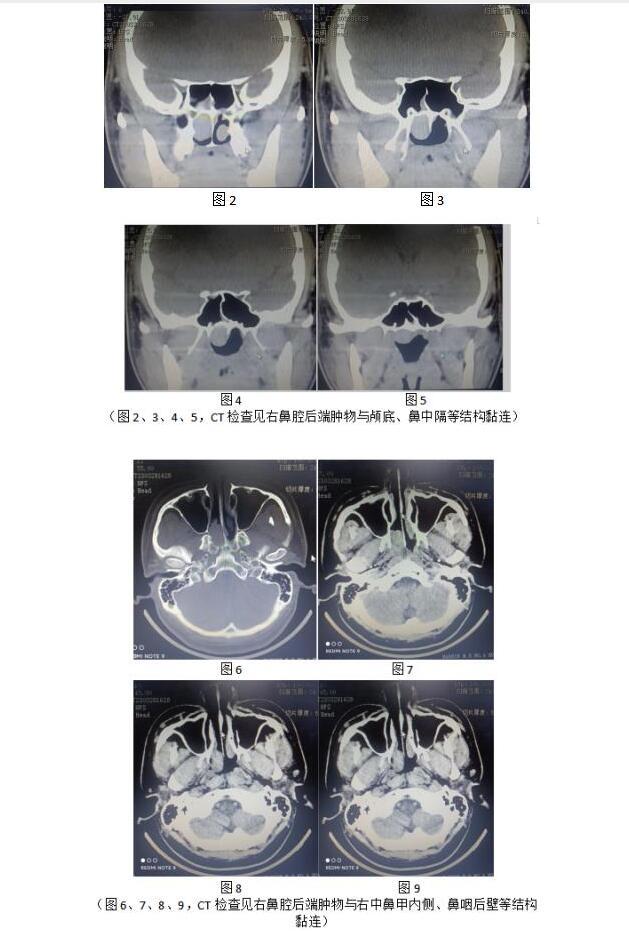

鼻窦CT检查见鼻咽部肿物占位,肿物大,位于鼻腔后端及鼻咽部,外侧与右中鼻甲内侧壁,内侧与鼻中隔右侧,上端与颅底,后端与鼻咽后壁黏连。